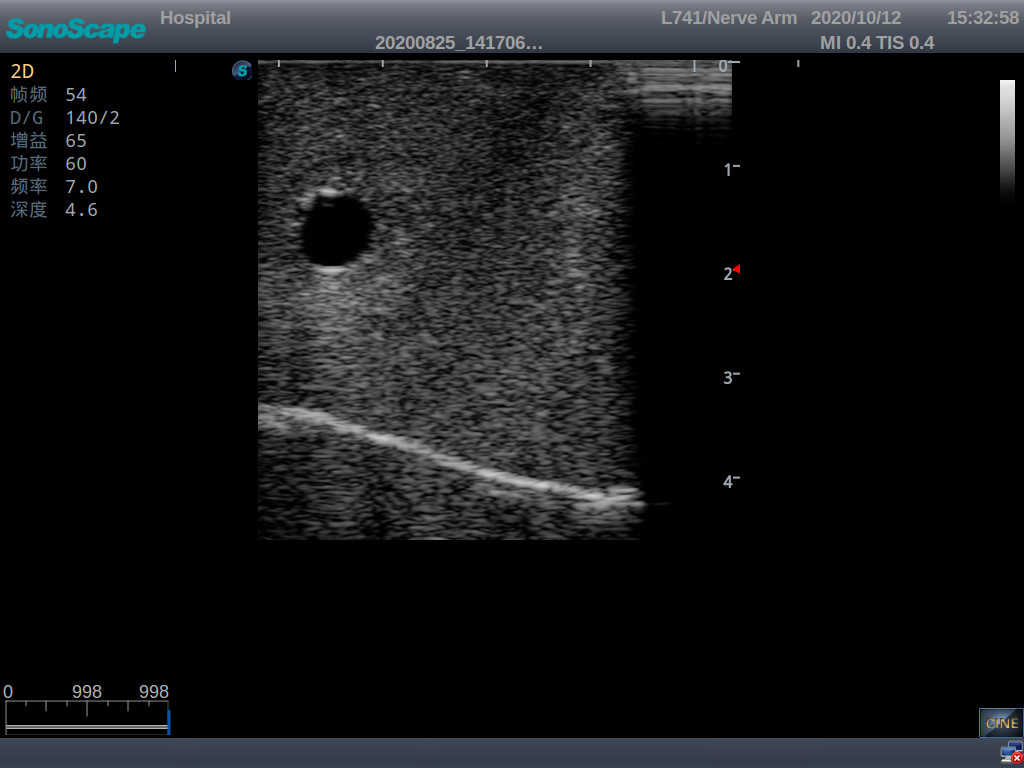

Central Venous Catheterization Ultrasound Training Model

Model TYE1510.2

Outline

It is a model from the earlobe plane to the umbilical plane with its head turned to one side. It's put in a standard central venipucture and catheterization position, including landmarks such as right arm, clavicle, ribs, sternocleidomastoid muscle, sternoclavicular joint, etc. It can be used for ultrasound-guided subclavian vein and internal jugular vein puncture and catheterization. The model's arm can be used for ultrasound-guided PICC catheter placement.

Skills Gained

· Subclavian vein puncture and catheterization

· Internal jugular vein puncture and catheterization

· PICC catheter placement

Features

· Anatomy:

Right internal jugular vein, right common carotid artery, superior vena cava, right brachiocephalic vein, right brachiocephalic trunk, right subclavian vein, right subclavian artery, etc.

· Key Features:

1)  The module for central venous catheterization is transparent, allowing users to clearly see the course and adjacent relationship of blood vessels

2)  The puncture module supports using a clinical real ultrasound machine to observe clear images such as right internal jugular vein, right common carotid artery, superior vena cava, right brachiocephalic vein, right brachiocephalic trunk, right subclavian vein, right subclavian artery, etc.

3)  The puncture pad at the arm is made of high-molecular ultrasound material, close to real skin. It can support the use of real ultrasound machines, and the images of tissue structures (skin, subcutaneous tissue, blood vessels) under ultrasound are clear and real

4)  A sense of “pop” can be felt when the vascular puncture is successful, and the outflow of venous blood can be simulated

5)  The guide wire’s march can be observed under the guidance of ultrasound, and also whether the catheter is placed correctly can be detected

6)   All the puncture modules are replaceable